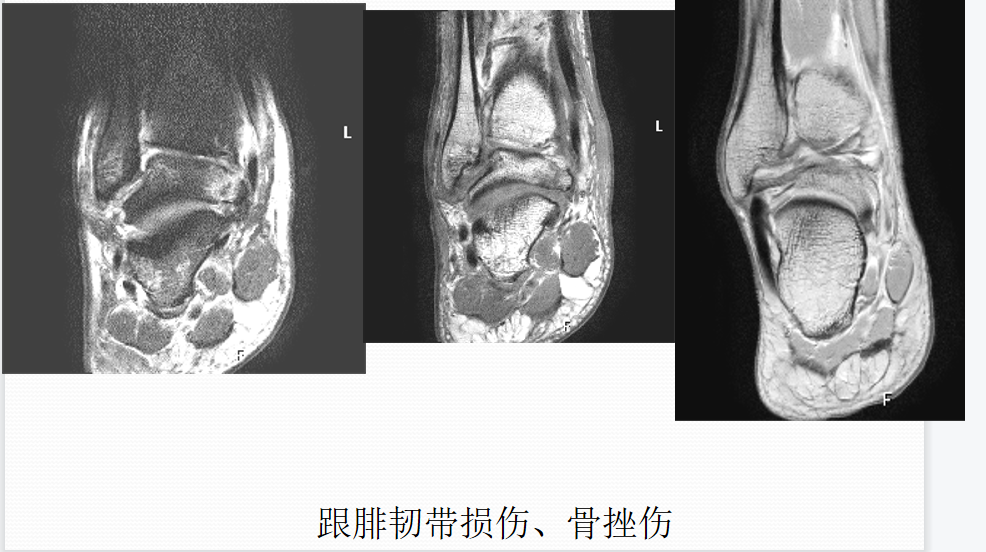

踝关节韧带损伤MR表现

直接征象

韧带形态学上改变:韧带走行、宽厚度异常;韧带边缘不光整;韧带连续性部分或完全中断;韧带信号异常改变

辅助征象

韧带周围结构改变:脂肪间隙及关节腔异常变化;其他邻近组织或结构的异常改变,包括:骨、软骨损伤、肌腱损伤、关节腔积液等。

距骨骨软骨损伤

病因病理机制:

• 距骨骨软骨损伤(OLT)是经软骨的骨折、骨软骨骨折、剥离性骨软骨炎和距骨穹窿骨折的通称。

• 直接创伤或反复微创

• 骨坏死过程导致软骨下骨折和塌陷

• 累及关节软骨和软骨下骨内侧(60%)和外侧(40%)